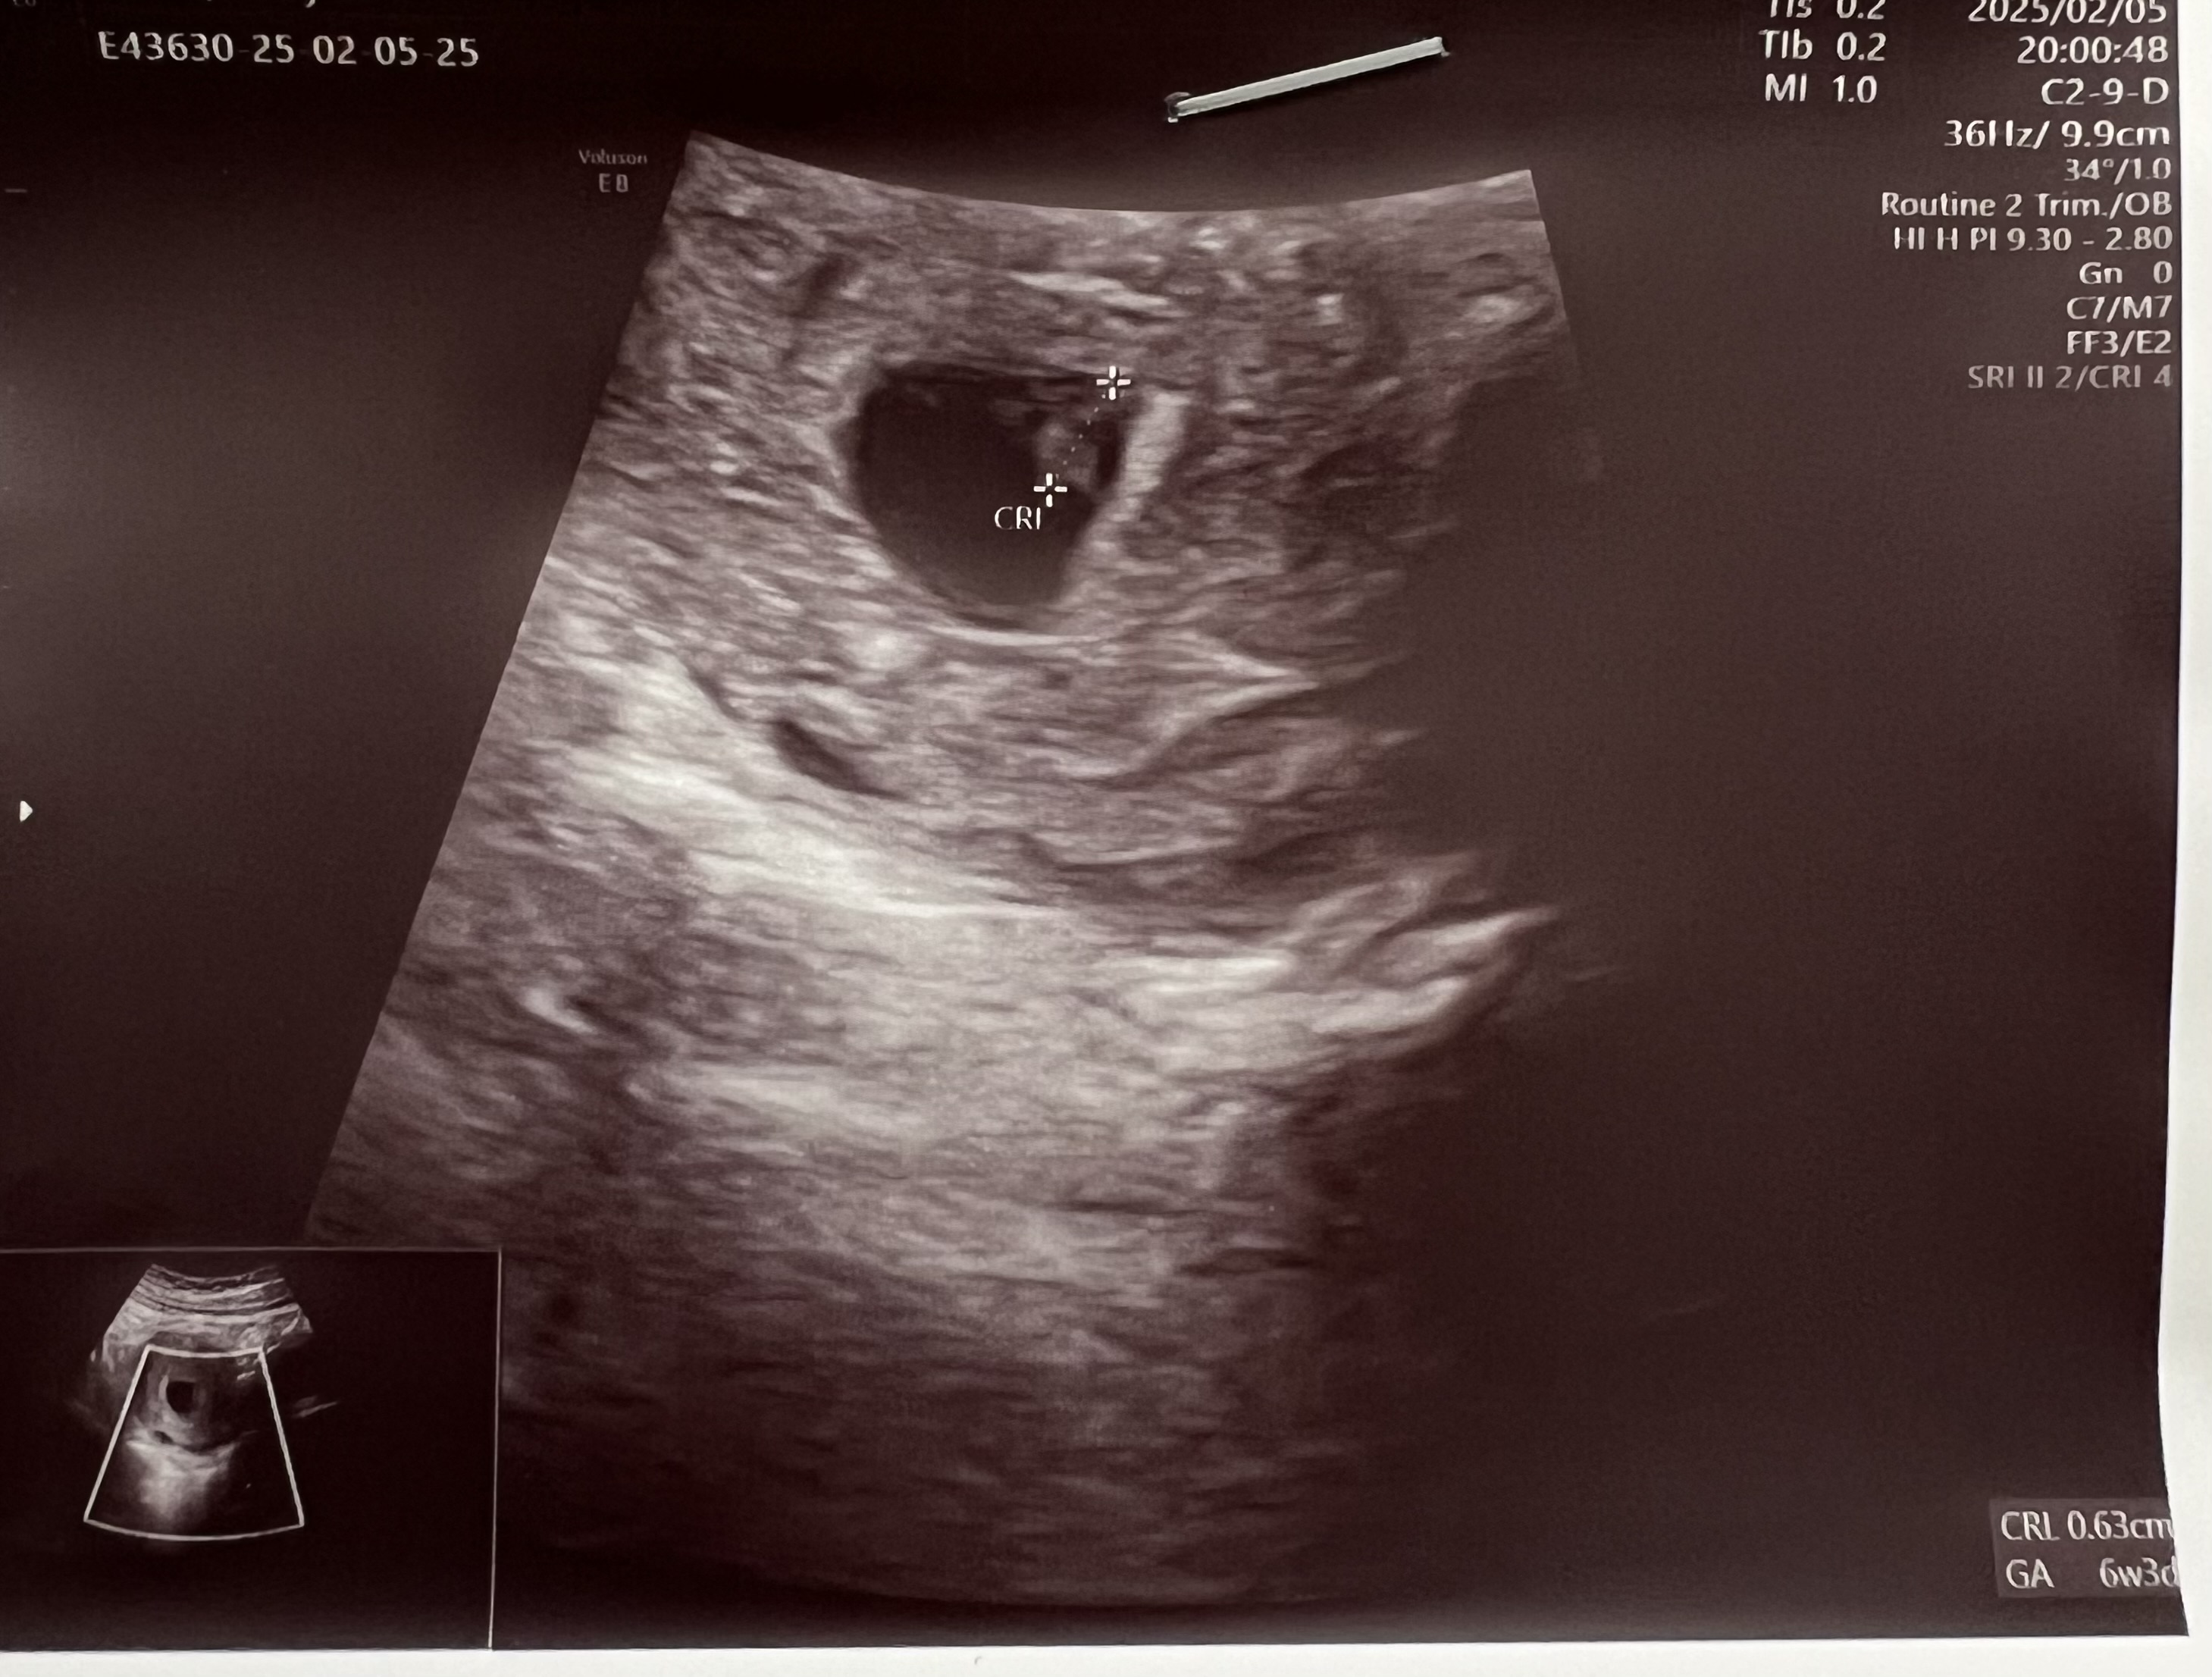

میگن اگه بچه سمت راست تصویر سونو قلب باشه یعنی سمت چپ مادر قرار گرفته و دختره

خواستم ببینم این فرضیه درسته؟